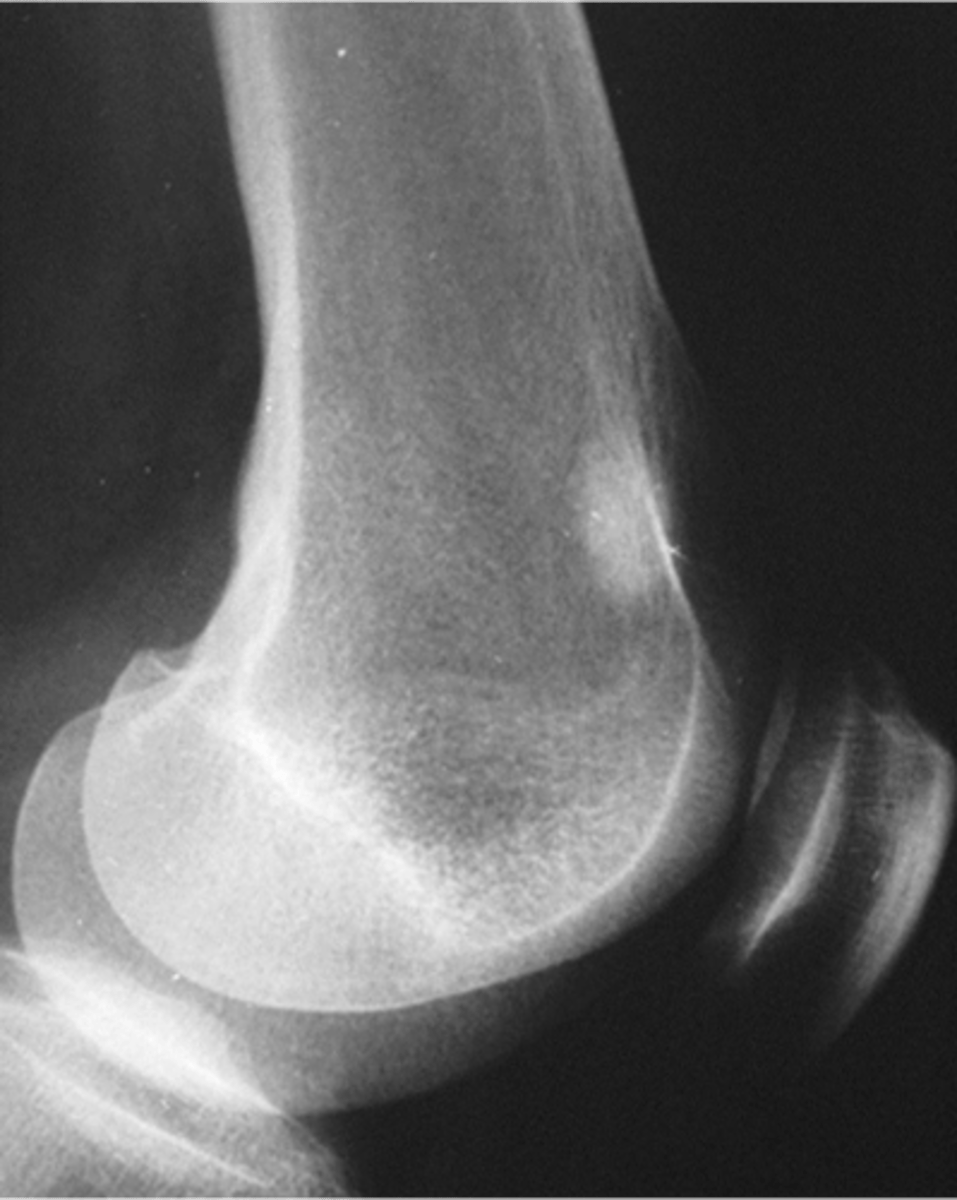

Cartilage cap

What is this?